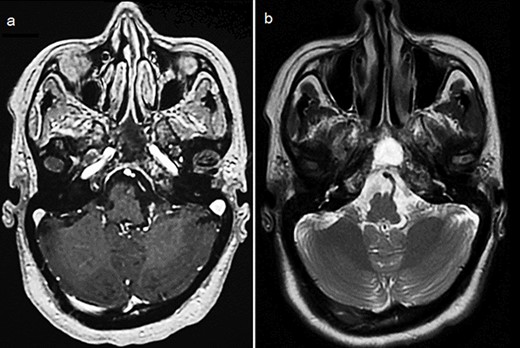

By the end of biological exploration, the patient reported a recurrence of headaches and blurred vision, 2 months after surgical decompression. Cerebral MRI revealed a relapse of the sphenoid plasmacytoma, measuring 70 mm (Fig. 3). Given the pathological diagnostic result, surgical re-intervention was not decided. Instead, the patient was treated with external beam radiotherapy (RTX) focused on the sphenoid bone (30 Gy), followed by immunochemotherapy with zoledronic acid. After 6 months, complete response was noted with the resolution of symptoms, disappearance of the monoclonal band, normalization of sFLC, and persistence of lytic sequelae on cerebral MRI (Fig. 4). Autologous stem cell transplantation (ASCT) was successfully performed, and the patient was put under treatment maintenance. After 18 months of follow-up, clinical, biological, and radiological evaluation confirmed sustained complete remission.

Cerebral MRI (axial views) showing a relapse of the sphenoid BP measuring 70 mm (a, b: T1 weighted post-gadolinium; c: T2 weighted).